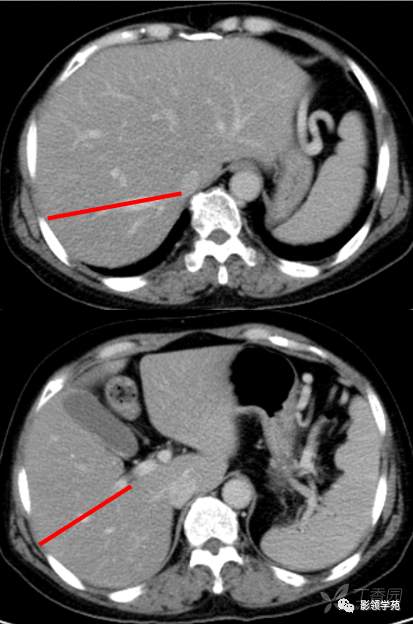

第二肝门下方层面CT横断面

第一肝门层面CT横断面解剖

CT:首先找出肝脏的三大静脉:肝中静脉,肝左静脉,肝右静脉,找出门静脉及其分叉部位。门静脉分叉部位可以区分上段和下段,即肝S8/S5,S7/S6,门静脉分叉以上为S8、S7;肝右静脉和肝中静脉之间是右前叶,肝右静脉以后是右后叶

一般规律,从CT上看,最先看到的是S8然后是S2、3,肝左外叶以肝裂为界,左内叶为肝裂和肝中静脉之间的区域,胆囊往下的层次是S5,最后的层面一般是S6,下腔静脉和门静脉夹着的是尾状叶,即S1。